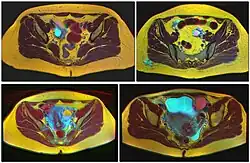

Ovarian cysts are usually diagnosed by pelvic ultrasound, CT scan, or MRI, and correlated with clinical presentation and endocrinologic tests as appropriate.[15] Ultrasound is the most important imaging modality, as abnormalities seen in a CT scan sometimes prove to be normal in ultrasound.[5][8] If a different modality is needed, then MRIs are more reliable than CT scans.[5]